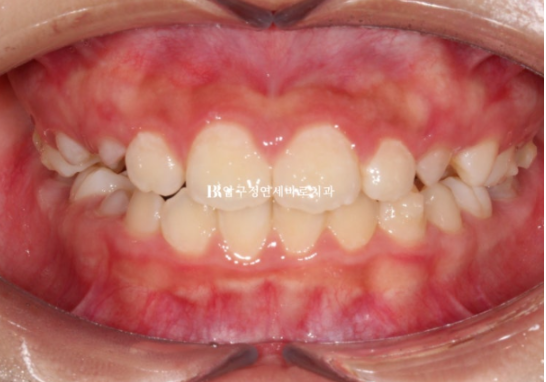

남은 시간을 계산해서 재제작 치료 계획을 세우고 추가장치 한 세트 더 낀 후 모습입니다.

추가장치는 24년 5월부터 11월까지 6개월 간 꼈습니다.

24.11

파란 화살표 측절치 배열이 잡히지 않아 들려있고 아랫니와 절단교합을 보이면서 이러한 교합간섭 때문에 중심선이 약간 틀어진 모습입니다.

인비절라인 장치를 껴보면 파란 화살표 측절치가 장치와 떠 있는 것이 보입니다.

장치 끼는 시작이 부족하여 인비절라인 장치가 치아를 잡아주지 못하고 놓쳐버린 것 입니다.

출국일이 두달 후로 임박했고 인비절라인 장치를 재제작할 시간은 없었습니다.

위 앞니 6개에 MTA 장치를 붙이고 중절치와 측절치 높이를 맞추는 과정을 한달간 거쳤습니다.

그리고 24년 12월에 치료를 마무리 하였습니다.

24.12

다행히 한달만에 배열이 잡히고 중심선은 잘 맞으며 측절치도 잘 내려왔습니다.